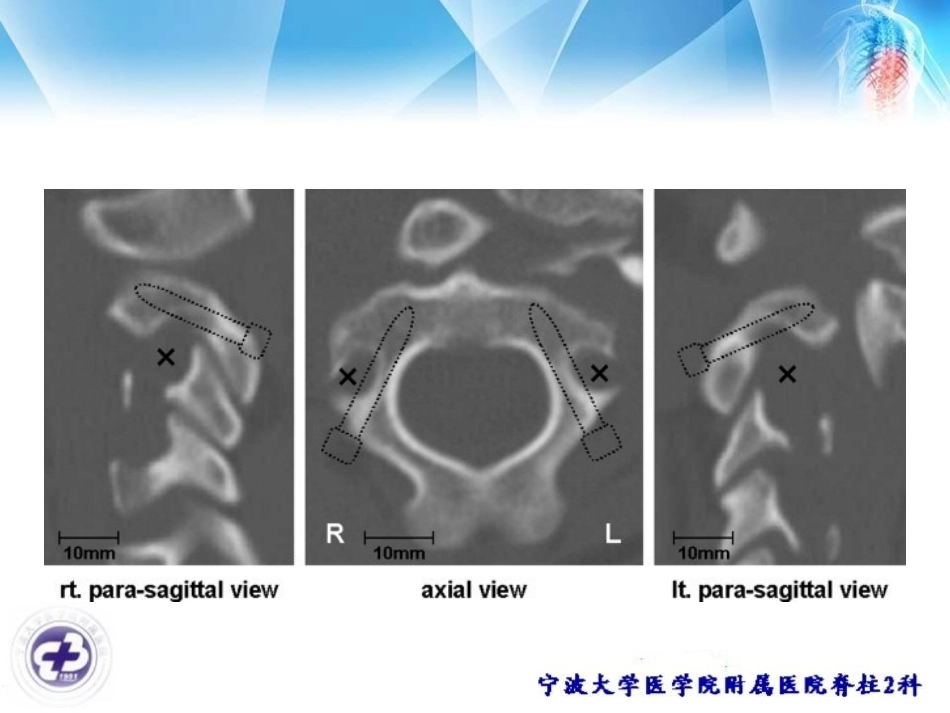

椎动脉高跨和颈2椎板螺钉(High-RidingVertebralArtery/C2laminarscrews)俞武良2018-3-21C2pediclescrewvertebralartery(VA)VAinjury•4.1%to8.2%forposterioratlantoaxialtransarticularscrewfixation•5.3%–21%forC2pedicularscrew•FactorscontributetoVAinjury–VAgroove(VAG)anomaly•high-ridingvertebralartery14.5%–18%•narrowC2pedicle9.5%–32%–insertionofthescrewextremelyclosetotheVA•HRVAdefinedashavinganisthmusheightof≤5mmand/oraninternalheightof≤2mmonthesagittalimage2–3mmlateraltothecorticalborderofthespinalcanalatC2.•narrowC2pedicledefinedashavingthelargestpedicularwidthof≤4mmontheaxialimagehigh-ridingvertebralartery(HRVA)•椎动脉在枢椎上关节突的下方有一个向外的弯曲,如果椎动脉弯曲过于向后、内或位置过高,则提示枢椎峡部狭窄,这种情况称为椎动脉高跨C2laminarscrew(Wright2004)我们最近的病例